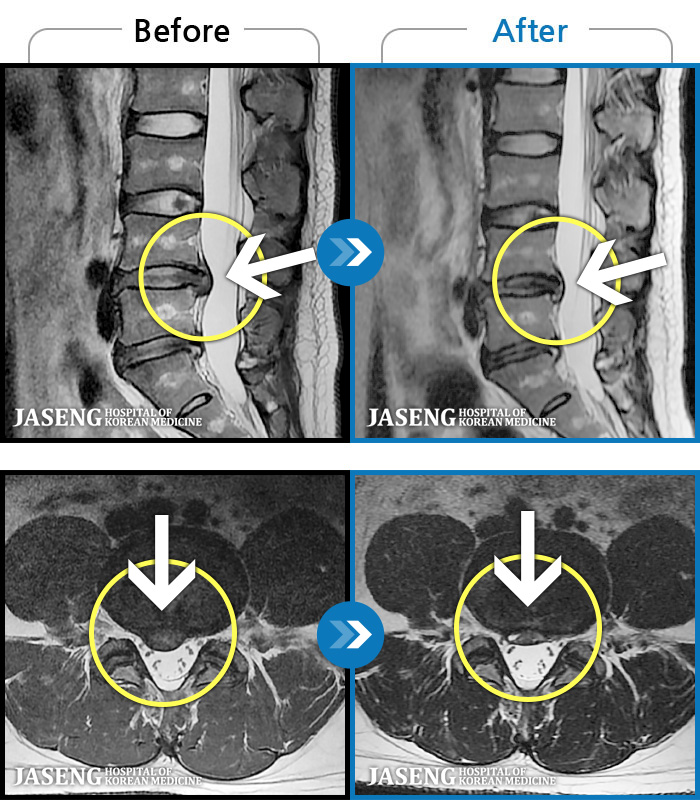

허리디스크

안산 · 조창현 원장

심한 허리 통증으로 내원

촬영시기

2025.04.22 ~ 2025.11.03

2025.11.07

조회수 168